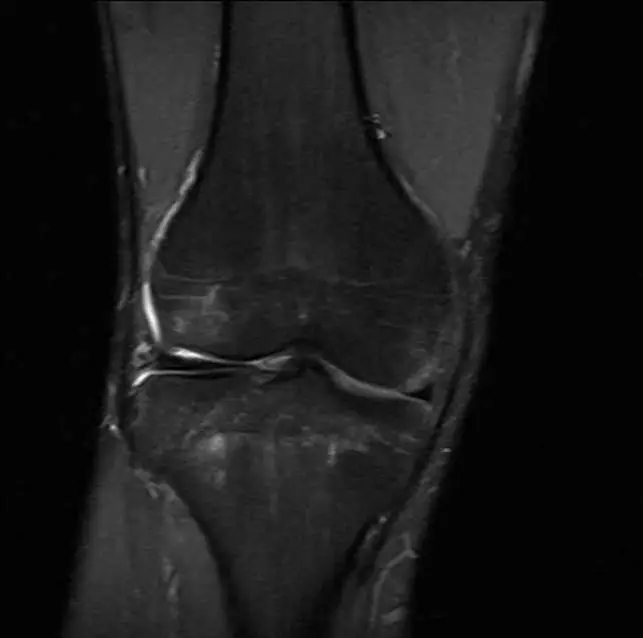

MRI 冠狀面 T2 fat-sat (或 STIR) 加重像

於